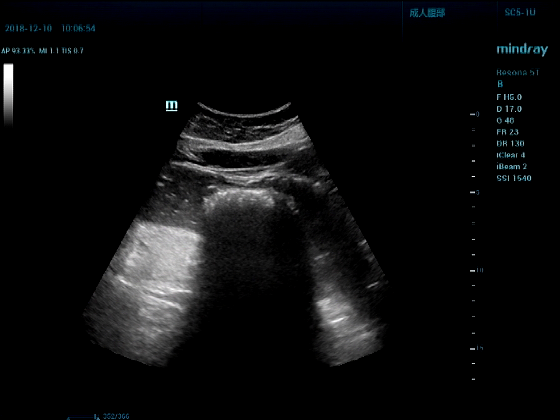

男,81岁,全身浮肿来住院

超声可见:左房,右房,右室明显增大,主肺动脉及右肺动脉增宽,二尖瓣中度反流,三尖瓣重度反流,肺动脉轻度高压,心律不齐

心包积液盆腔积液。淤血性肝增大,肝静脉增宽。(右心衰声像改变)